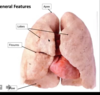

Identify the indicated features of the lungs

Idenfity the indicated surfaces & borders of the lung

Surfaces are neme for the structures they contact through the

pleura

- costal

- contacts pleura near thoracic wall

- daphragmatic surface

- base of lung

- mediastinal surface

- hilum of lung & slightly concave

- anterior border

- costal and mediastinal surfaces meet up

- sharp - into costal mediastinal recess

- inferior border

- costal and diaphragmatic surfaces meet up

- goes into costaldiaphragmatic recess

- posterior border

- costal and mediastinal surface meet up

- rounded - in paravertebral gutter